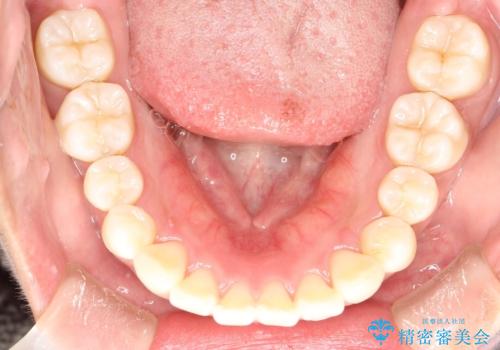

がたがたをインビザラインで整った歯並びへ

- 全体的ながたつきを主訴に来院されました。

抜歯矯正も考えられる状態でしたが、患者様が非抜歯での矯正を希望されたため、歯と歯の間をわずかに削りスペースを作り、全体を整える計画としました。

非常に協力的な患者様でしたので、スムーズに治療を終えることができました。